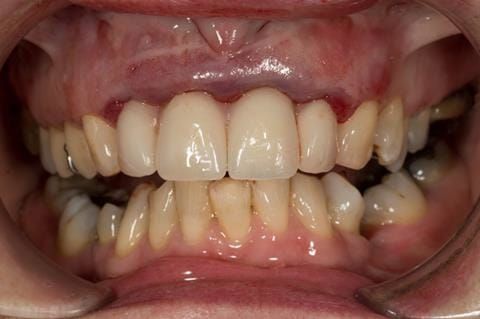

- UR2 peri-radicular periodontitis with a peri-radicular area on the root apex. Retrograde amalgam filling from a previous apicectomy. No visible root canal or root canal filling. Large circumferential marginal gap between the crown and tooth. Large post and core present. Very little tooth structure remaining resulting in a fragile tooth with increased potential for fracture.

- UR1 peri-radicular periodontitis with a small peri-radicular area on the root apex with wide blunderbuss apex. Radio-opaque root canal filling present approximately 3 mm short of the radiographic apex. Large circumferential marginal gap between the crown and tooth. Large post and core present. Very little tooth structure remaining resulting in a fragile tooth with increased potential for fracture.

- UL1 peri-radicular periodontitis with a peri-radicular area on the root apex. Retrograde amalgam filling from a previous apicectomy. Visible root canal space with no sign of root canal filling. Large circumferential marginal gap between the crown and tooth. Large post and core present. Very little tooth structure remaining resulting in a fragile tooth with increased potential for fracture.

- UL2 peri-radicular periodontitis with a peri-radicular area on the root apex. No visible root canal or root canal filling. Large circumferential marginal gap between the crown and tooth. Large post and core present. Very little tooth structure remaining resulting in a fragile tooth with increased potential for fracture.

- High smile line showing gum above gingival zeniths of upper front teeth when smiling. Aesthetic failure of the upper four incisors with inflammation of the gingivae and mis-match of the gingival zenith levels.